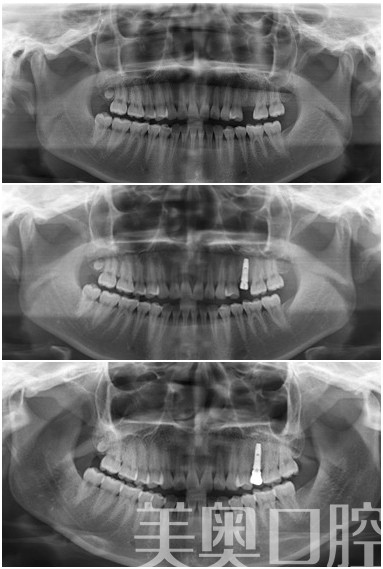

美奥(苏州)5S即刻种植牙

技术推荐:奥齿泰种植牙、瓷睿刻技术

患者感受:我种牙很顺利的,种时一点也不痛,后来挂了一次水防止发炎,但实际上没有问题。恢复得也好。不是种植问题。现在美奥口腔还是会定期给我联系,咨询牙齿的使用情况以及如何保护,这点我很满意。

美奥点评:奥齿泰种植牙是比较经济的一款种植牙系统,价格容易接受,但是瓷睿刻技术是一种即刻修复技术,造价比较昂贵,对于时间充裕的患者,可以选择普通的全瓷冠来修复。